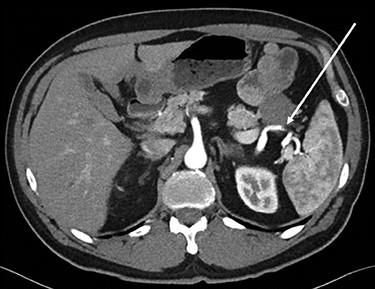

Abdominopelvic CT scan disclosed a 3.7-cm mass, between the tail of the pancreas and the splenic hilum, causing a narrowing of the splenic vein and splenomegaly (Figs 1–3).

Sagital CT scan of abdomen, selected image from a pancreatic protocol, late arterial/pancreatic phase. A 3.7-cm mass, between the tail of the pancreas and the splenic hilum, causing a narrowing of the splenic vein and splenomegaly (arrow).